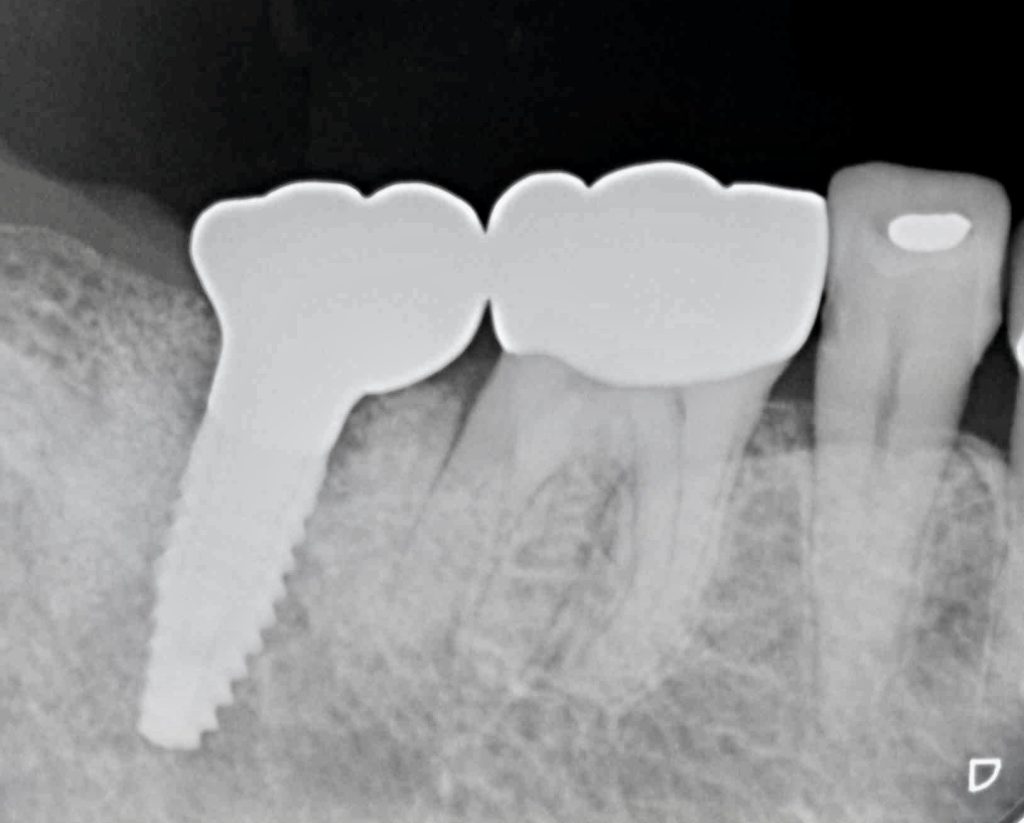

今回、古いメタルインレーの中でカリエスが進行し、骨縁下まで進行していました。

抜歯と同時にインプラント埋入手術を行い、4ヶ月ほどで治療を完了いたしました。